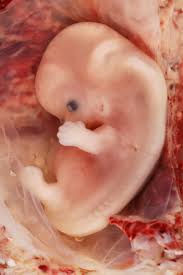

Early Sonography

Before 10 weeks

WHAT DOES IT TELL ABOUT MY BABY SO EARLY?

- It tells you the exact duration of pregnancy.

- It rules out pregnancy lying outside the uterus at early stage to safeguard your life.

- It tells you whether it is single or multiple pregnancies (Twins / Triplets).